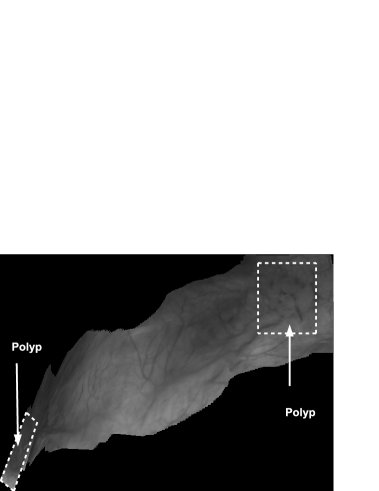

Figures 4 and 5 show two panoramic images constructed from real cystoscopic examination images using and respectively. The panoramic image in Figure 4 is a 1479 1049 pixel image constructed from a 450 image sequence using . In this panoramic image, two polyps are visible on the top-right and at the bottom left of the image. Both polyps can be accurately located in relation to each other. Figure 5 represents a 650 182 pixel panoramic image constructed from a 500 cystoscopic image sequence using . There are no visible discontinuities on texture affirming a quite good visual coherence.